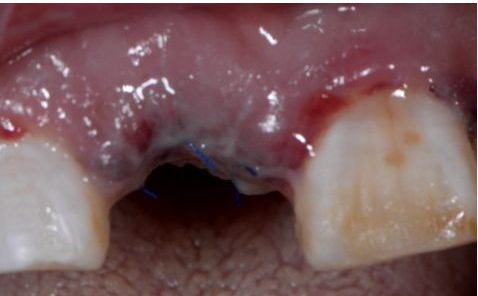

在口腔種植領域中,由于各種原因造成的種植牙局部牙槽突骨量不足或種植體周圍骨缺損的修復在種植外科的研究中已經取得了重大突破。新一代的血漿提取物--濃縮生長因子(CGF,Concentrate Growth Factors)能夠明顯縮短術區成骨的時間,提高成骨質量,促進成骨及組織的愈合;具體有:引導骨再生技術、聯合骨膜表面覆蓋加速軟組織愈合、用于上頜竇提升、拔牙后即刻種植、牙槽嵴位點保存、頜骨囊腫的治療、牙槽骨修整。